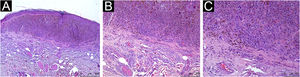

Todos os pacientes avaliados apresentaram IIT, com diferentes classificações qualiquantitativas (tabela 2). IIT moderado a marcado esteve presente em 54,5% do CM e em 68% do CNM. Para os dados brutos, obteve‐se um odds ratio (OR) de 0,57 (95% IC 0,18‐1,8; p=0,338). A análise multivariada com ajustes para índice de Breslow, sexo e idade ao diagnóstico do melanoma foi aplicada, e a presença de IIT moderado a marcado apresentou OR de 0,68 (95% IC 0,13‐3,99; p=0,669). As figuras 1, 2 e 3 mostram imagens histopatológicas de IIT leve, moderado e marcado em paciente com MCPF.

Os dados do presente estudo não conseguiram atestar a proteção do IIT para o desenvolvimento de metástases, pois todos os pacientes avaliados, com e sem metástases, apresentavam o infiltrado. Ainda que os pacientes com MCPF não metastático apresentassem mais frequentemente IIT moderado a marcado, quando comparados aos pacientes metastáticos – 67,9% vs. 54,5%; respectivamente – não houve demonstração de significância estatística (OR=0,68; p=0,669).